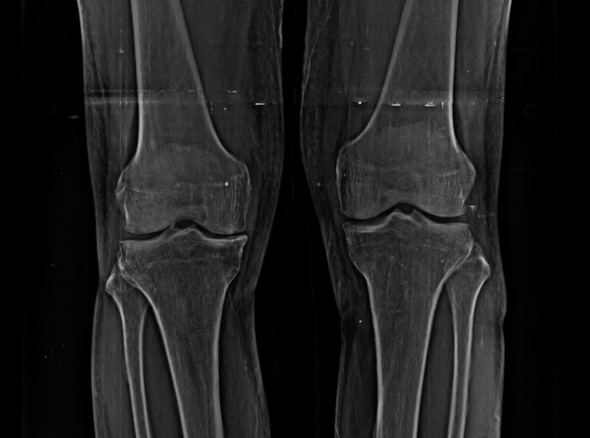

노화로 인해 연골이 닳아 통증,

운동 제한이 발생하는 경우

(계단 오르내리기, 구부리기, 쪼그려 앉기 등)

퇴행성관절염은 치료의 시기가 매우 중요합니다.

한번 진행이 시작되면 피하기가 어려워 치료가 빠를수록 진행을 최대한 늦출 수 있습니다.